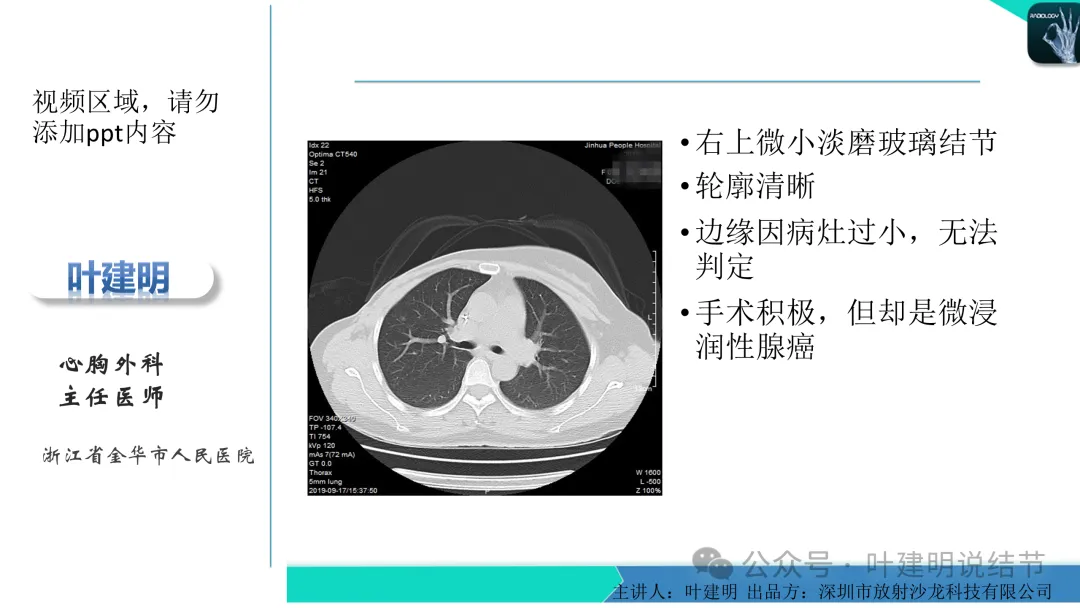

右上叶淡磨玻璃结节,才3-4毫米许,还很小,而且密度非常低,不过轮廓较清,边缘无膨胀性,像肺泡上皮增生。

左下叶结节,轮廓稍显模糊,邻近有血管走行,无血管弯征,病灶中间密度稍低,结节密度很淡,仅小片状模糊影似的。

右上叶与左下叶这两处结节均密度很低,非常淡,而且瘤肺边界并不是特别清晰,考虑少许肺泡上皮增生可能性大,目前没有什么风险,可常规年度复查随访。不能太着急,也不必太着急干预处理。我一直强调不要管最后病理是什么,而是从影像上判断风险如何、纯不纯,密度高不高,还能不能观察。你这种不单密度低,还小,不需要过分担心的,安心随访便可。意见供参考!

这个病灶会是微浸润性腺癌吗?当然没有病理诊断,我也不能说百分之百必不会,但这样的病灶已经风险大到必得尽快手术切除干预了吗?显然还早着呢:1、影像不是典型的结节状;2、边缘与轮廓模糊不清;3、灶内似有细支气管扩张(更容易是细支气管扩张伴少许周围炎或肺泡上皮增生);4、血管邻近走但无牵拉影响;5、没有实性成分,没有锐利毛刺,没有胸膜牵拉,没有血管进入,没有任何倾向风险性高的影像特点。我一直强调:肺结节是否要干预处理,不要纠结于最后病理是什么,而要看风险高低;而风险高低的最重要术前判断依据一是随访有无进展,二是有没有实性成分。只要没有肉眼可见的影像上的实性成分,风险就是低的!何况病理也是人看的,原位还是微浸润,不典型增生还是原位有时也在一念之间。